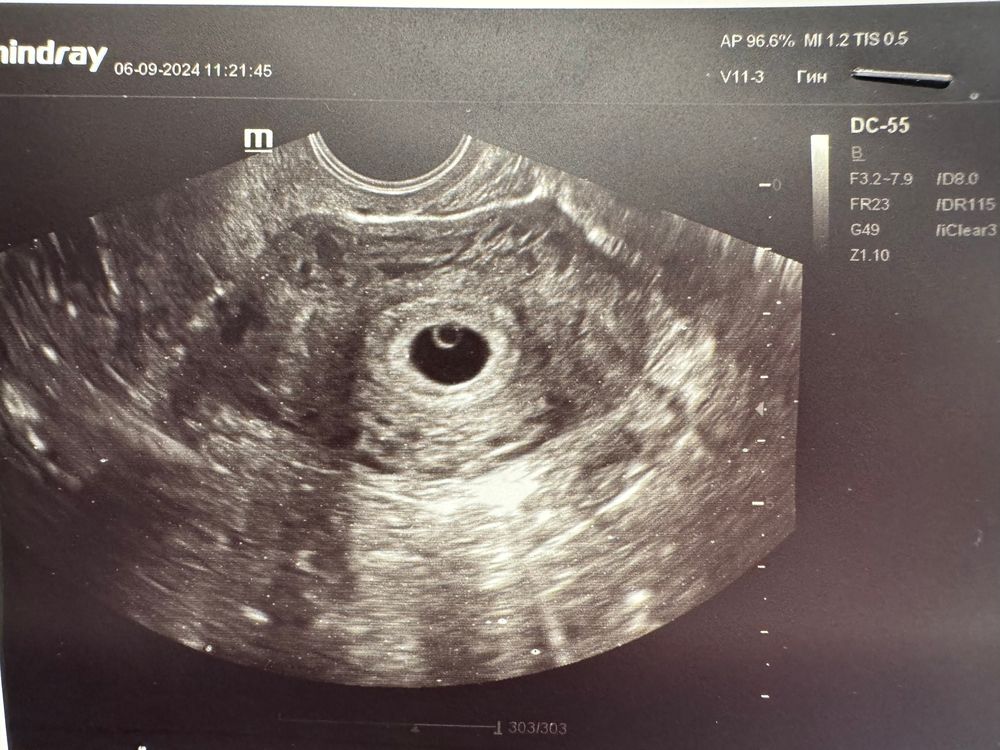

Марина, в меня все лезет 🤣 я жру как слон. Еще и желчный начал шалить, у меня загиб. Накупила бананов. Ем их каждый час по одному маленькому иначе вообще крутить начинает от боли если голодной ходить. Сыров еще много ем. Яйца вроде как полезно, надо купить и варить а то я и правда проглот какой то стала. Муж уже смотрит косо)) это пожалуй единственное что поменялось. Одни перекусы да чаепития. До ужина за час бутерброды после ужина через час бананы. Куда все девается не понимаю только. А вот груди и тошноты нет. Поэтому и побежала на узи. Хоть и рано но вчера хгч был 11 тысяч и я надеялась увидеть хотя бы точку на месте эмбриона. Так оно и получилось)) желаю и вам поскорее встретиться с вашим ❤️ это волшебно и сразу успокаивает)

7я неделя, пью Дюфастон. Жутко тошнит Узи 7-8 недель